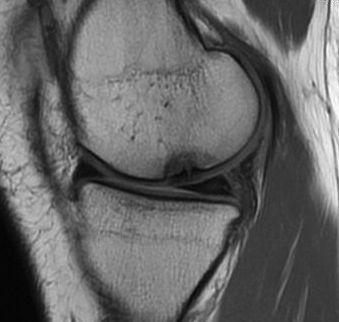

Cartilage defects

• Cartilage defects